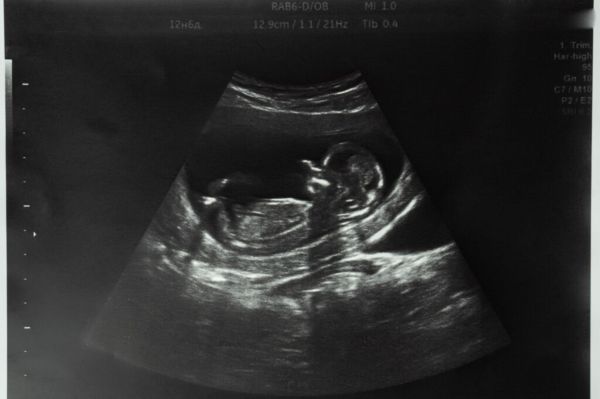

2025年12月22日,波多黎各(Porto Rico,美國的一個聯邦自治邦)總督Jenniffer Gonzále簽署183-202號法律,承認未出生孩子的法律人格(la personnalité juridique)。該法案主要由參議院議長Thomas Rivera Schatz起草,文本規定,未出生的孩子「無論在母親子宮內處於任何妊娠階段」,都被視為一名「自然人」 (personne physique )。

她指出,這些新法律帶來的「根本性改變」,在於「明確承認自受孕起人類生命的尊嚴,作為一個民族,這一點恢復了我們在1952年制定憲法時所確立的道德基礎」。她回顧說,波多黎各憲法「明確承認生命權,而根據制憲時期的立法討論,這項承認的目的很清楚,就是為了保護母親子宮內的人類生命」。

Joanne Rodríguez進一步指出:「透過承認未出生孩子為自然人與法律主體,並把對孕婦的攻擊、且導致胎兒死亡的行為定義為一級謀殺,我們不僅承認了母親子宮內孩子的人性,也承認其作為人的尊嚴。」這位參議員接著表示:「這不僅關乎新法律意涵的重要性,以及法律施行所帶來的實際後果,更是一種在本體論層面上的深刻轉變。」她最後總結道:「訊息非常清楚:在孕婦的子宮內,並不存在一個沒有尊嚴、模糊不清的東西,而是一個主體,一個正在發展中的人類,具有尊嚴,其價值內在於其人性本身。」